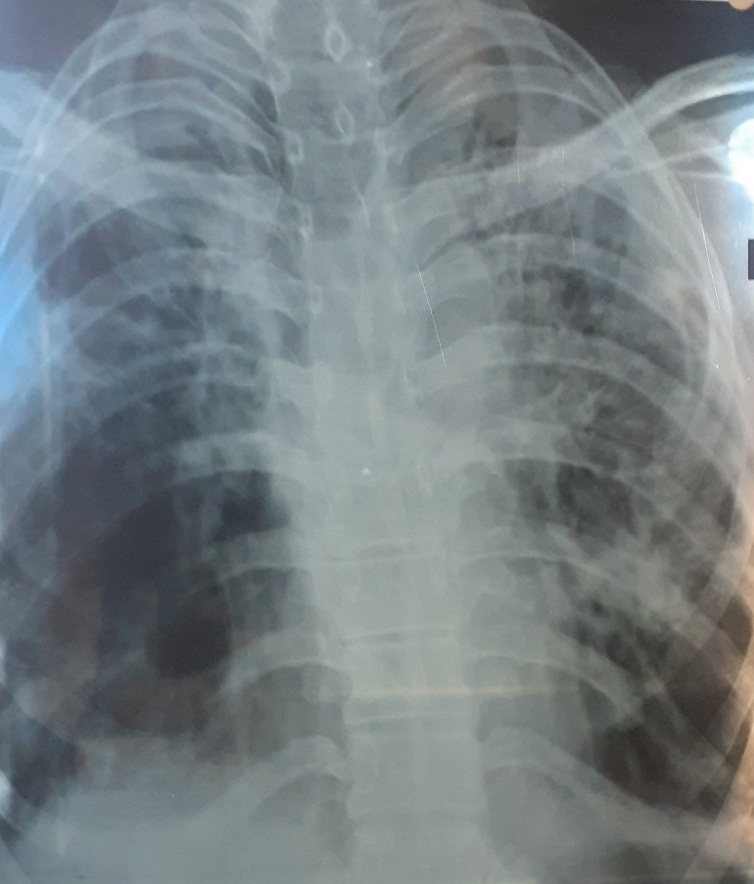

~Chest Xray: revealed fibrotic changes in both lung field, more marked in left lung.

- Chest X-ray: Chest X-rays can be used to evaluate for lung involvement, including interstitial lung disease, which can appear as hazy shadows on the X-ray.

- CT Chest: High resolution CT chest can provide detailed images of the chest and can be used to evaluate lung involvement, including interstitial lung disease and pulmonary arterial hypertension.